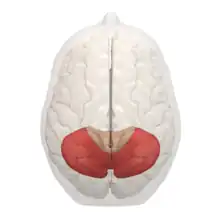

Desde el punto de vista filogenético, el cerebelo puede dividirse en tres porciones: arquicerebelo, paleocerebelo y neocerebelo. Esta división es de gran interés porque cada una de las porciones posee cierta identidad funcional y clínica.

El arquicerebelo. Es la porción filogenéticamente más antigua y se corresponde con el lóbulo floculonodular. Surge durante el desarrollo filogenético al mismo tiempo que el aparato vestibular del oído interno. La mayoría de aferencias que recibe provienen de los núcleos vestibulares y se corresponde en gran medida con el vestíbulocerebelo. Tiene una función de equilibrio.

El paleocerebelo. Es más moderno que el arqueocerebelo y está integrado por la pirámide, la úvula, el lobulillo central con las alas, el culmen y el lobulillo cuadrangular. La mayoría de las aferencias que recibe provienen de la médula espinal y tiene cierta correspondencia con el espinocerebelo. Tiene una función de control postural.

El neocerebelo. Es la parte más moderna y está formado por la totalidad del lóbulo posterior a excepción de la pirámide y la úvula. La mayoría de las aferencias que recibe provienen de la corteza cerebral a través de los núcleos del puente y se identifica con el cerebrocerebelo. Tiene una función de coordinación motora (movimientos voluntarios).